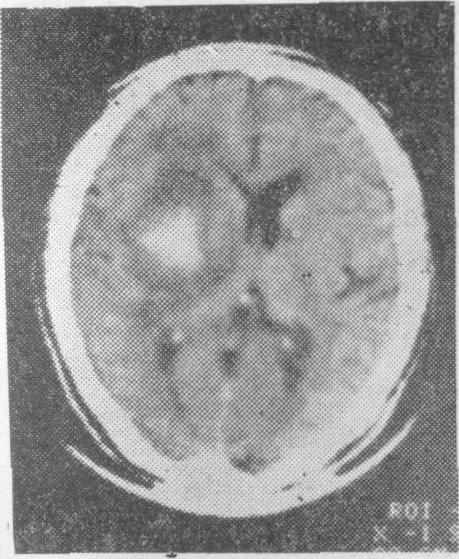

老年人脑血管病的诊断主要依靠详细询问病史,仔细观察临床症状和体征,并结合各种筛选检查。一般先用非创伤性检查,如脑电图、脑超声波、Doppler超声波、放射性核素脑扫描或计算机X线体层脑扫描检查等。特别是后者对老年人急性脑血管病的鉴别诊断更有帮助,可以鉴别是脑出血性病变(图3),脑缺血性病变(图4),抑或脑部肿瘤,以后根据需要再进行创伤性检查,如脑血管造影等。

图4脑缺血性病变的计算机X线体层脑扫描右侧枕叶有密度明显减低的缺血性病灶